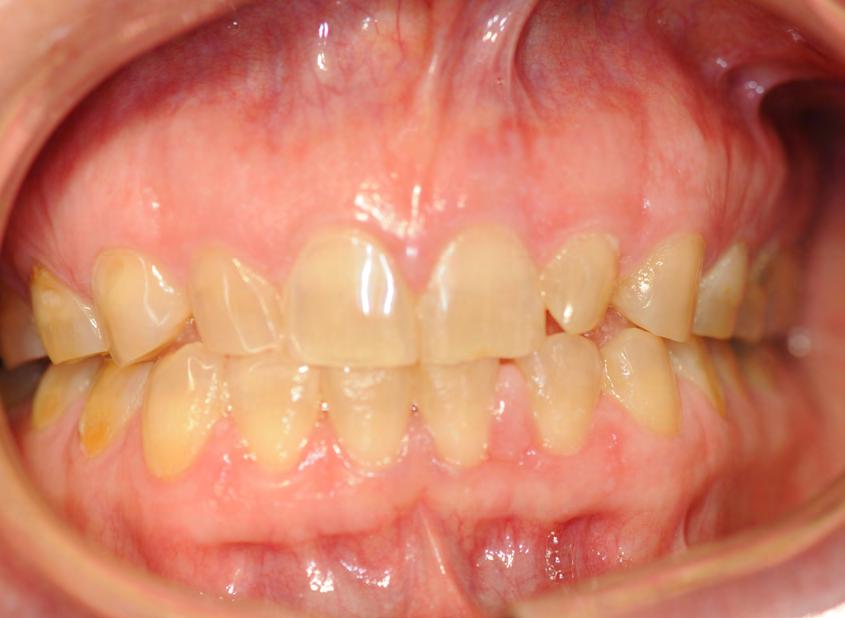

Two authors had access to the data and all information was de-identified. Study personnel made no contact with patients at any time throughout the study, and no PHI was recorded. Re corded data included diagnosis (clinical and/or pathologic), basic demographics (age, gender), and current prescription medica tions. For cases that were not biopsy-proven, the standard clinic protocol is that the clinical presentation must exhibit the charac teristic white Wickham striae for a patient to be given the clinical diagnosis of OLL or OLP (Figure 1). Any clinical diagnosis of OLL or OLP was rendered by one of four oral medicine experts in the Oral Medicine Clinic, and biopsy was performed in cases with any doubt.

Figure 1. Example of characteristic Wickham striae and reticular pattern on buccal mucosa used to clinically diagnose OLL and OLP cases. Erythematous areas also seen. Figure 2. Frequency and percent of study patients using specific medications with color-coded drug classes.